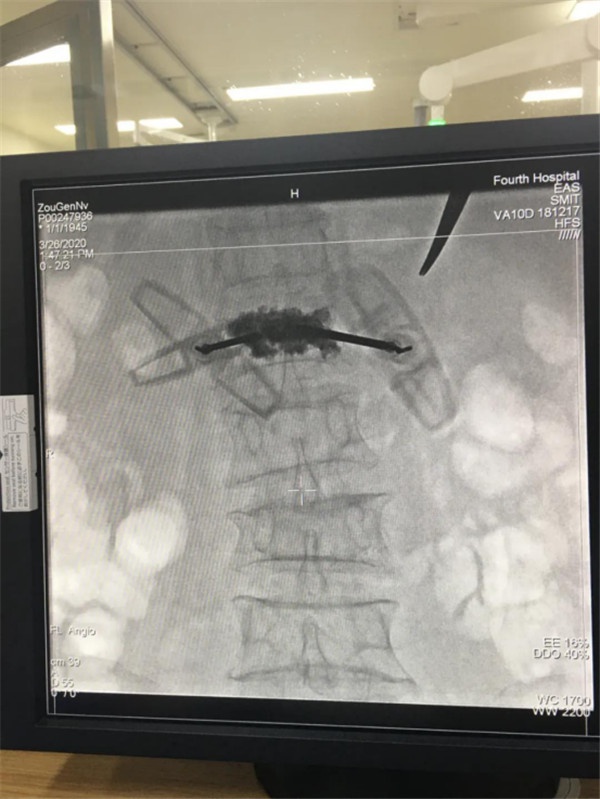

3月26日上午十點(diǎn),新余第四醫(yī)院DSA介入治療室,骨科何東生主任醫(yī)師采用DSA(數(shù)字減影血管造影)精準(zhǔn)定位,為一位75歲骨折老人患者行經(jīng)皮椎體后凸成形微創(chuàng)手術(shù),僅半小時手術(shù)取得成功。這臺手術(shù)的成功標(biāo)志新余第四醫(yī)院將DSA微創(chuàng)介入高新技術(shù)應(yīng)用于骨科臨床,為廣大中老年骨病患者帶來了福音。

術(shù)前DR